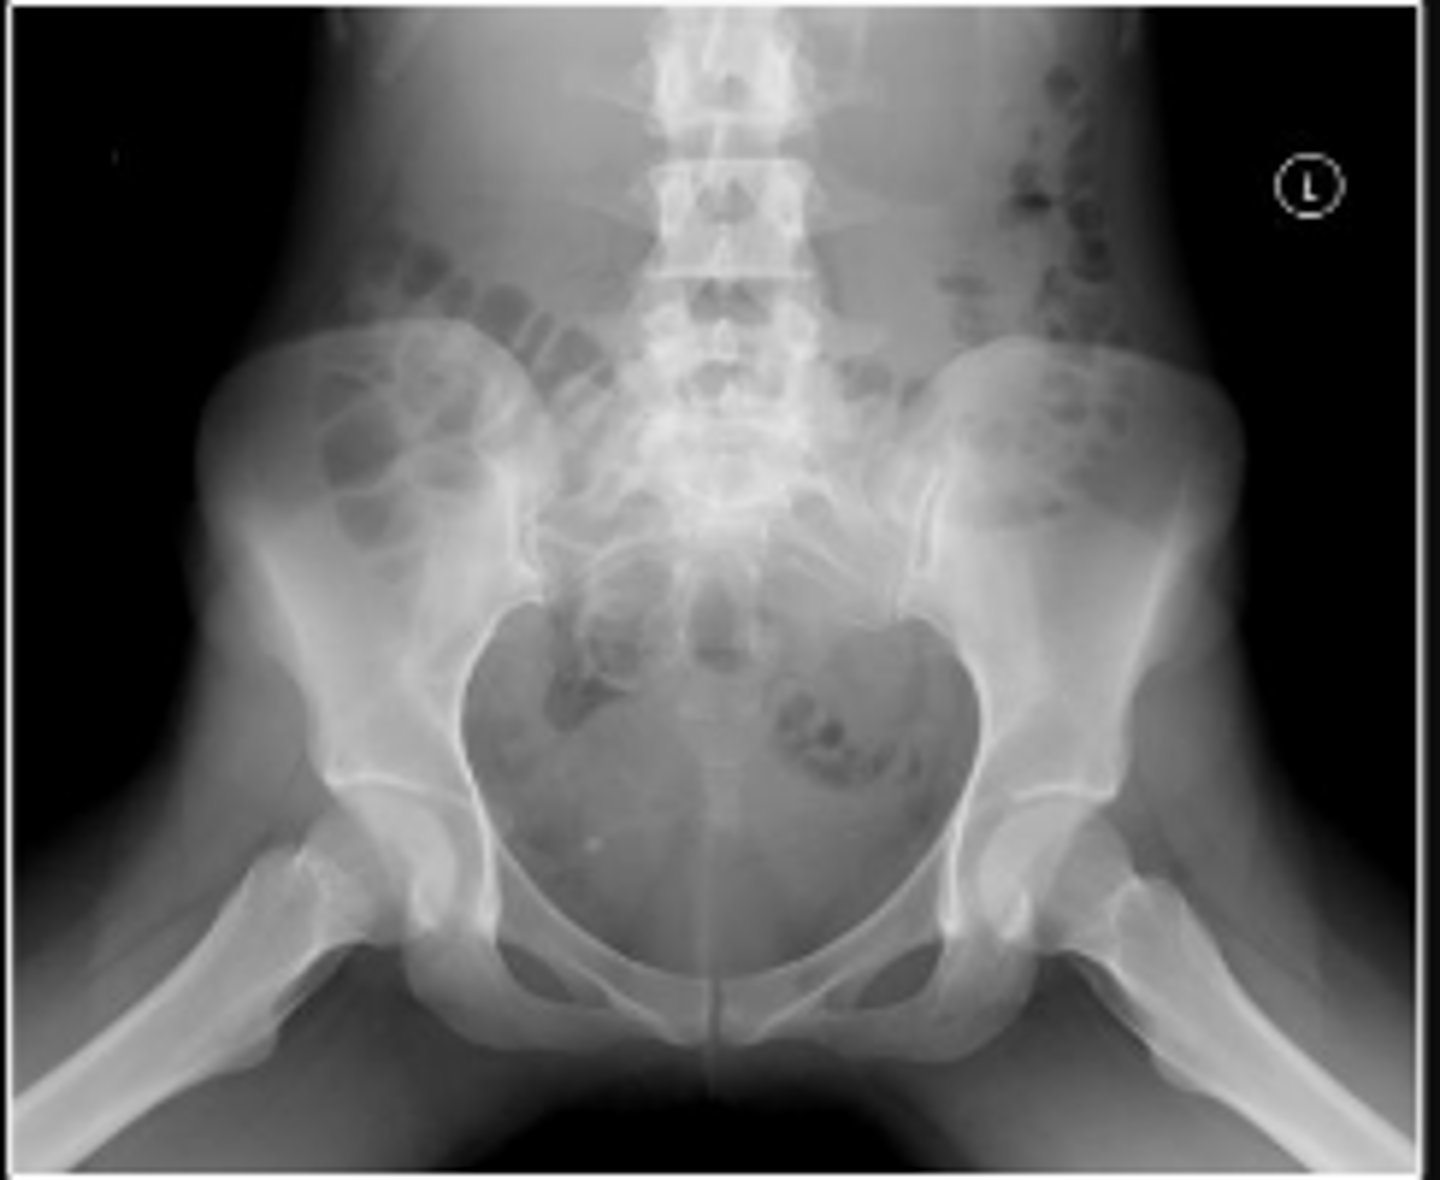

AP pelvis or bilateral hips

Name the radiographic view

Shenton's line

What is the name of the assessment?

From the undersurface of the femoral neck

continued to the inferior aspect of the superior

pubic ramus

What are the osseous land marks for this assessment?

Hip dislocation, fracture

Name 2 conditions that may result in an abnormal assessment?

Posterior hip dislocation

What is most significant radiographic finding?

Femoral angle

120-130 degrees

What is the normal range for this assessment?